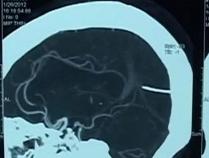

三歲男孩腹部凸起,醫(yī)生檢查發(fā)現(xiàn)在他的胃中居然有未成形的胎兒,也就是所謂的寄生雙胞胎。